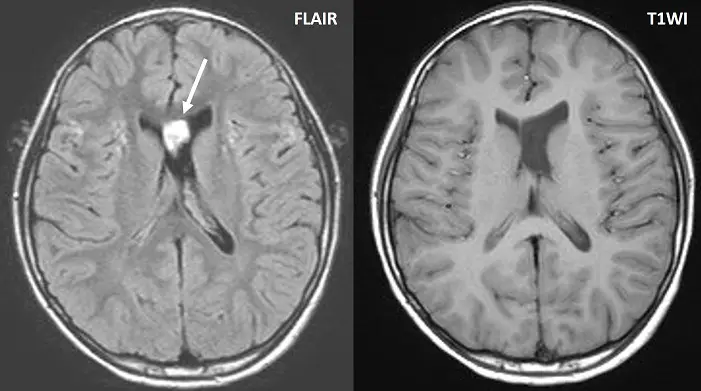

下圖中 FLAIR影像左側腦室內有一個白的訊號如箭號處,此應為:

- FLAIR 影像:在軸切面(axial)的 FLAIR 影像中,白色箭號指著左側側腦室(lateral ventricle)靠近室間孔(foramen of Monro)的位置,呈現一個局部且明顯的高訊號(hyperintensity)亮點。

- T1WI 影像:在同一解剖假面的 T1WI 影像中,雙側側腦室內的腦脊髓液(CSF)均呈現均勻的低訊號(hypointensity,呈現黑色)。箭號對應的位置沒有任何軟組織腫塊、不正常的結構佔位,也沒有異常的訊號變化。

- 綜合判讀:由於在解剖結構對比極佳的 T1WI 上完全沒有實質病灶的特徵,而在 FLAIR 上卻出現高訊號,這強烈提示該訊號並非實質的病理異常(如腫瘤或出血),而是與磁振造影技術相關的假影(artifact)或血流生理現象。

本題主要測驗磁振造影中 FLAIR(Fluid-Attenuated Inversion Recovery)序列的成像原理及其常見假影。FLAIR 利用特定的反轉時間(Inversion Time, TI)來消除(nulling)純水或靜止的腦脊髓液(CSF)訊號。然而,在腦脊髓液流動較快或產生擾流的特定解剖區域,流動現象(flow phenomenon)會導致未被完全消除訊號的液體進入切面內,進而產生假性高訊號,這在臨床影像判讀上是